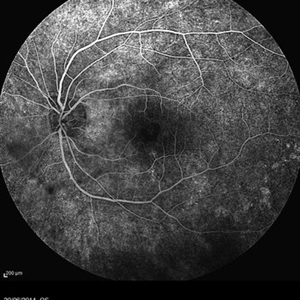

A fluorescence angiogram of a 40-year-old-man with a Behcet's Disease on his both eyes. This image was taken with ultra wide field lens (102 degree).

Photographer: Avris Romario Diparaja Siahaan, Klinik Mata Nusantara

Imaging device: Heidelberg Spectralis

Condition/keywords: ultra-wide field imaging